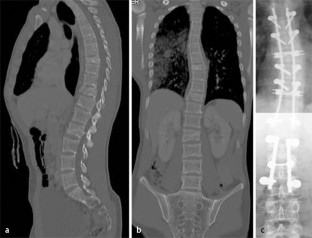

Abb. 1